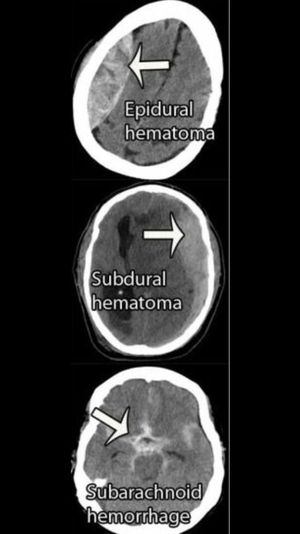

Types of hematomas shown on CT

In relation to the previous post

Trauma

Ct

Hematoma

Cranial